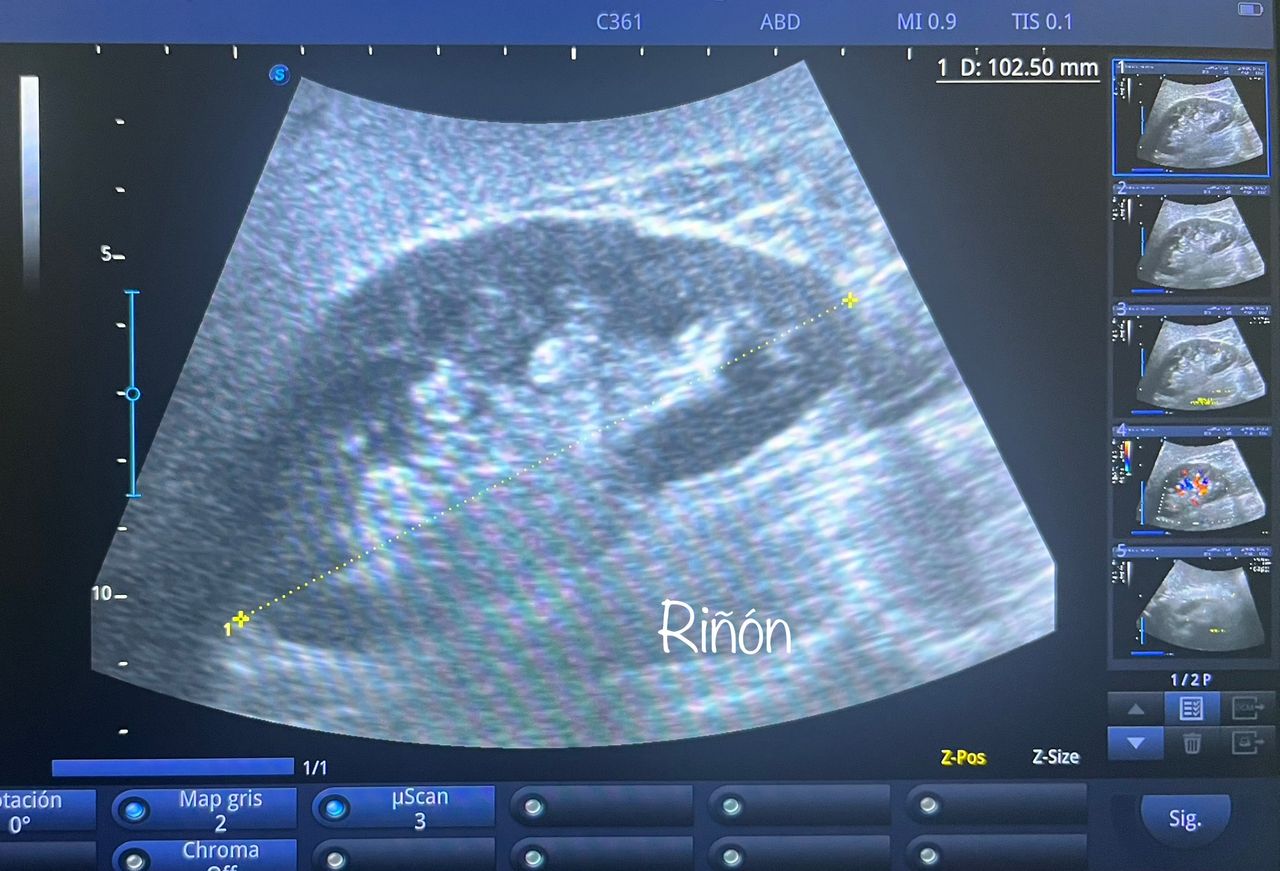

Médico general con 15 años de experiencia, master en enfermedades infecciosas y antibioticoterapia por parte de la Universidad Cardenal Herrera en Valencia, ademas de diversos diplomados en el área de Infectología y Parasitología, Urgencias, Imagenología y Medicina del Trabajo. He laborado en Hospitales y Clínicas en el área de Urgencias, en Laboratorios realizando estudios de Imagen, en especifico ultrasonidos de todo tipo desde básicos hasta avanzados incluidos los obstétricos estructurales, en Secretaría de Salud del Estado de Querétaro realizando ultrasonidos obstétricos para la detección de malformaciones en los tres trimestres del embarazo en diversos centros de salud, como médico de Empresas en el campo de Salud Laboral y actualmente en este consultorio en donde para su mejor atención y siempre buscando integrar la mayoría de las herramientas diagnosticas cuento con equipo de ultrasonido como apoyo en la exploración del paciente o como servicio diagnostico por imagen, realizo ultrasonidos convencionales (hepatobiliar (hígado, páncreas, vesícula y bazo), vías urinarias, ginecológico abdominal y transvaginal, tiroideo, prostático, testicular, pared abdominal) y especializados (dopler obstétrico en los 3 trimestres de embarazo), musculoesquelético en lesiones deportivas. También cuento con un equipo de electrocardiograma de 12 derivaciones para monitoreo completo del funcionamiento cardiaco, espirometria para evaluar la función pulmonar en la consulta, pruebas rápidas que se realizan en consultorio para detectar de forma mas precisa enfermedades infecciosas como Influenza A y B, covid19, infecciones urinarias, dengue, zika, chikungunya. Cuento con diversas vacunas para prevención de enfermedades. Siempre con el objetivo de dar el mejor servicio y atención a su salud. Lo espero en consulta para escucharlo y estudiar su caso de la forma más completa posible, estoy seguro de que tendremos las mejores opciones para su tratamiento. Mi tranquilidad es que usted se vaya con todas sus preguntas e inquietudes resueltas.

• Ultrasonio de riñones

$800